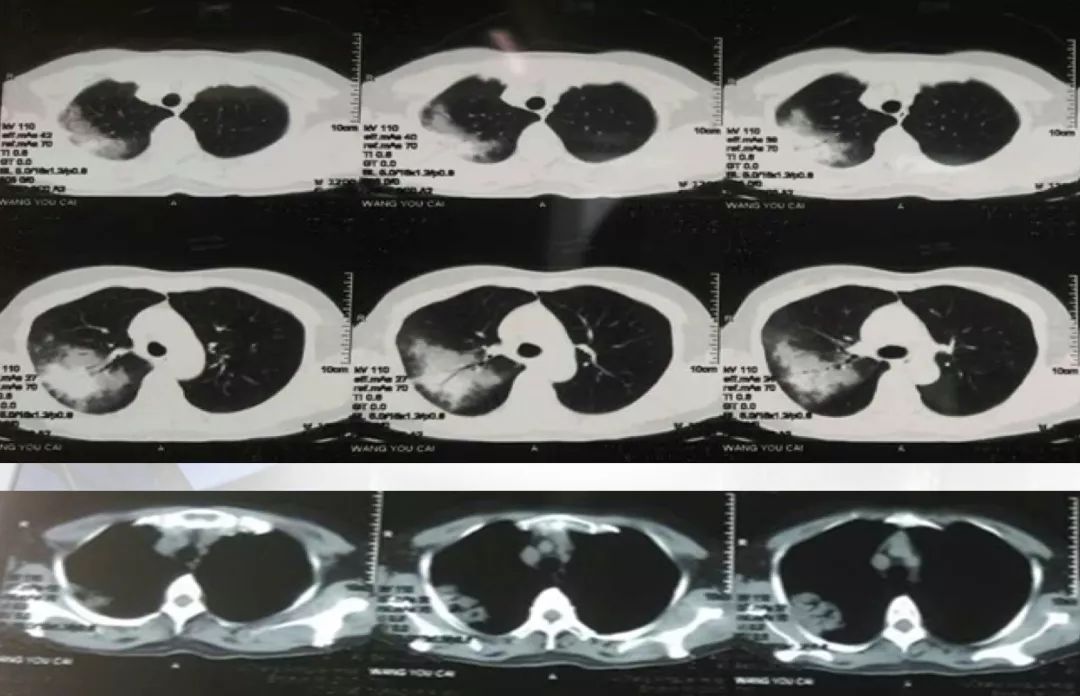

患者起病时2017-1-15胸部CT病变主要在右肺上叶后段,表现为大片状高密度影,可见支气管气象,提示支气管内不是阻塞性病变,病灶内有实变,周围有渗出性改变,纵膈窗和肺窗差别比较大,说明病灶密度不是非常高;

2017-1-23胸部CT病灶从范围来看是逐步扩大的,仍可见支气管气象,周围渗出更加明显,纵膈窗来看病灶总体密度增高,影像学表现总体提示病灶进展;

2017-2-5胸部CT:整体病变范围与2017-1-23号CT变化不大,但整体密度呈减低趋势,纵膈窗影像密度与肺窗差别较大,说明病变呈好转趋势;

2017-3-5胸部CT右上肺大片状高密度影消散,仅留下少许高密度条索影,但左肺上叶后段出现新发病变,但与之前右肺上叶病变影像学特征有所不同,之前三次影像学病灶密度是比较均匀的,此次左肺上叶后段病变,除了实变之外可见类空洞样改变,仍有支气管充气征,周围见细条索影,右下肺背段见类结节影像。

> 影像学检查:起病表现为右上叶后段斑片状高密度影,伴部分实变,可见支气管充气征,抗感染治疗后右上叶病灶完全吸收,新出现左上肺团片影,周边磨玻璃影,及右下肺背段不规则团块影。